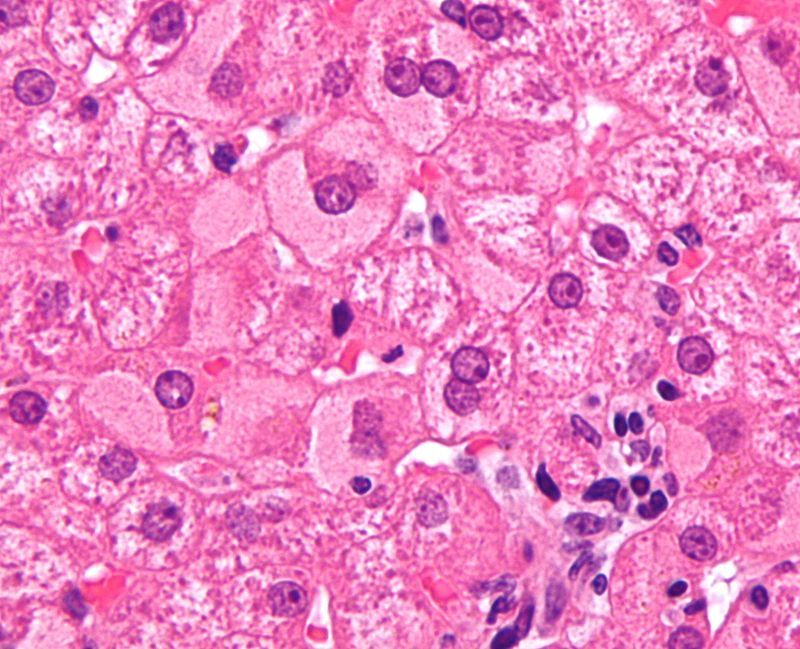

Small, ovoid bodies within macrophages is characteristic of which fungus?

Histoplasma capsulatum